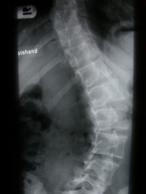

Die Früherkennung von Haltungsfehlern und Gelenkerkrankungen im Kindesalter stellt eine wichtige Voraussetzung zur Vorbeugung und Verhütung orthopädischer Beschwerden im späteren Alter dar. Zu den Untersuchungen zählen u.a. die Feststellung eventueller Haltungs- und Gangbildauffälligkeiten, die Beurteilung der Fußstatik zur frühzeitigen Vermeidung von Spätschäden sowie die Behandlung von akuten Gelenkbeschwerden. Sportmedizinische Beratung für Kinder Endgrößenbestimmung Durch die Röntgenaufnahme der linken Hand ist es bei Kindern ab dem 6. Lebensjahr möglich, die zu erwartende Endkörpergröße zu bestimmen und ggf. frühzeitig bei Riesen- oder Minderwuchs therapeutisch einzugreifen.